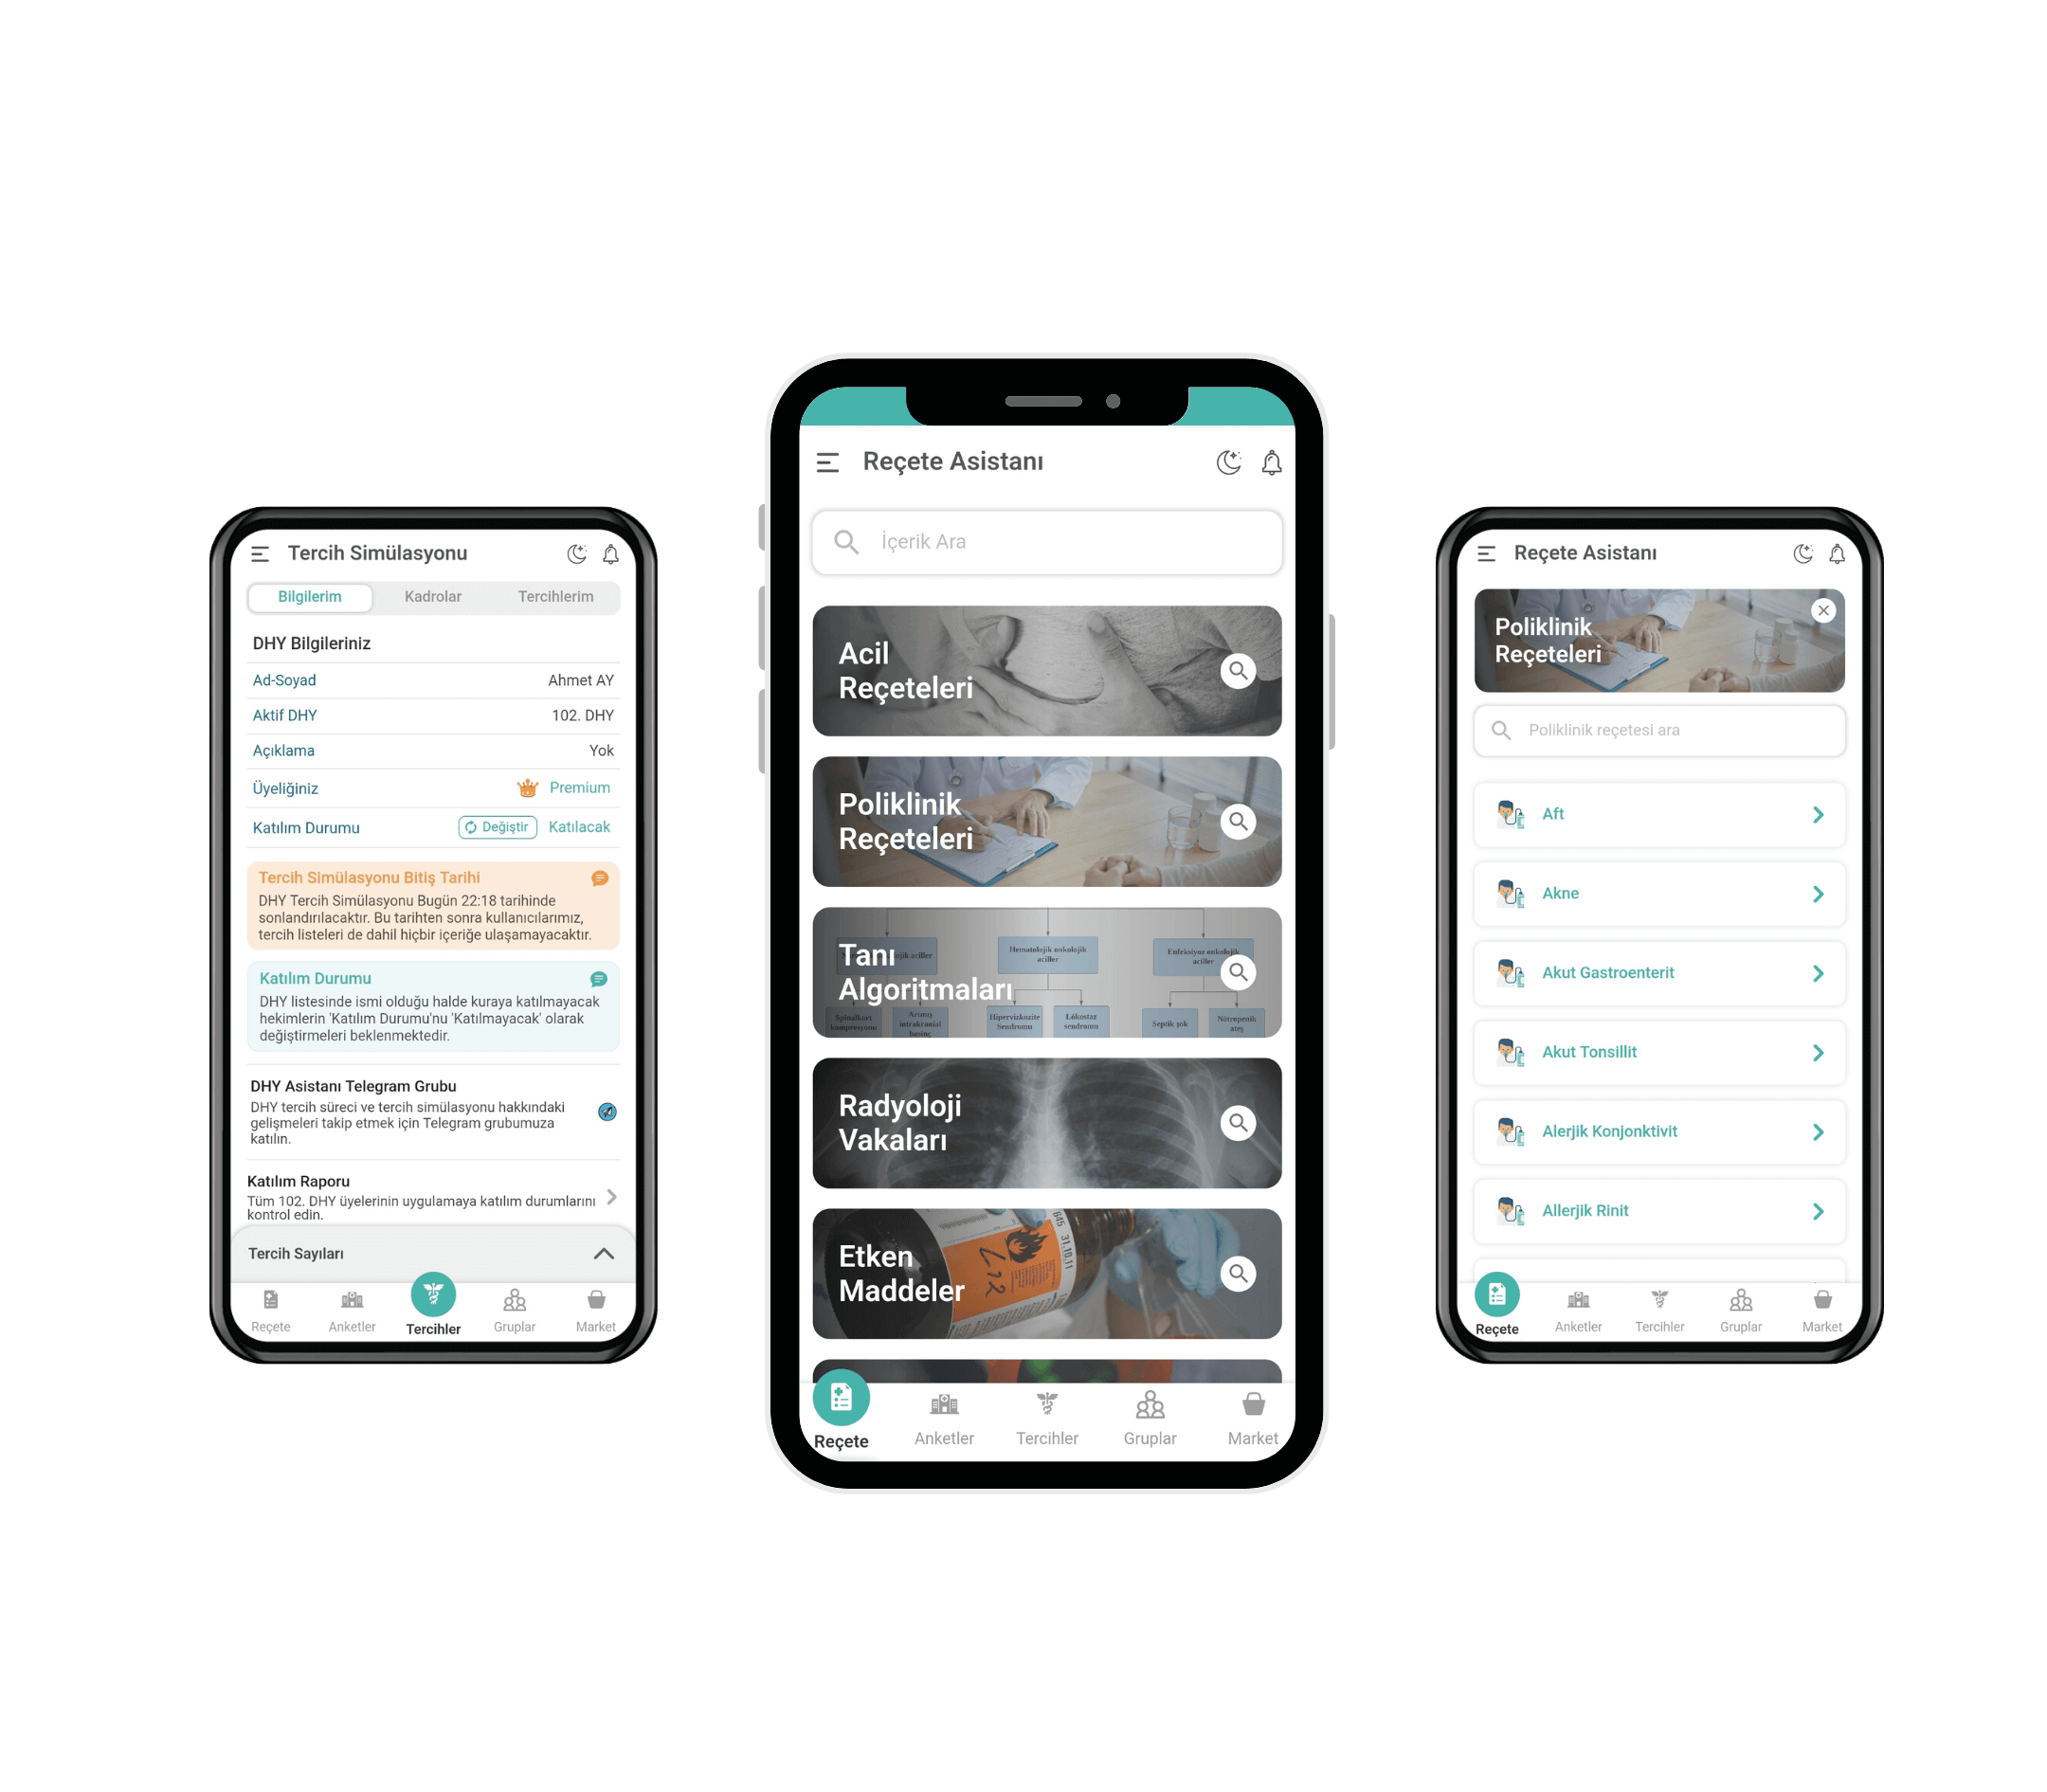

We've combined all your needs for exam preparation in the Plexia app.

Complete coverage of all topics in medical literature